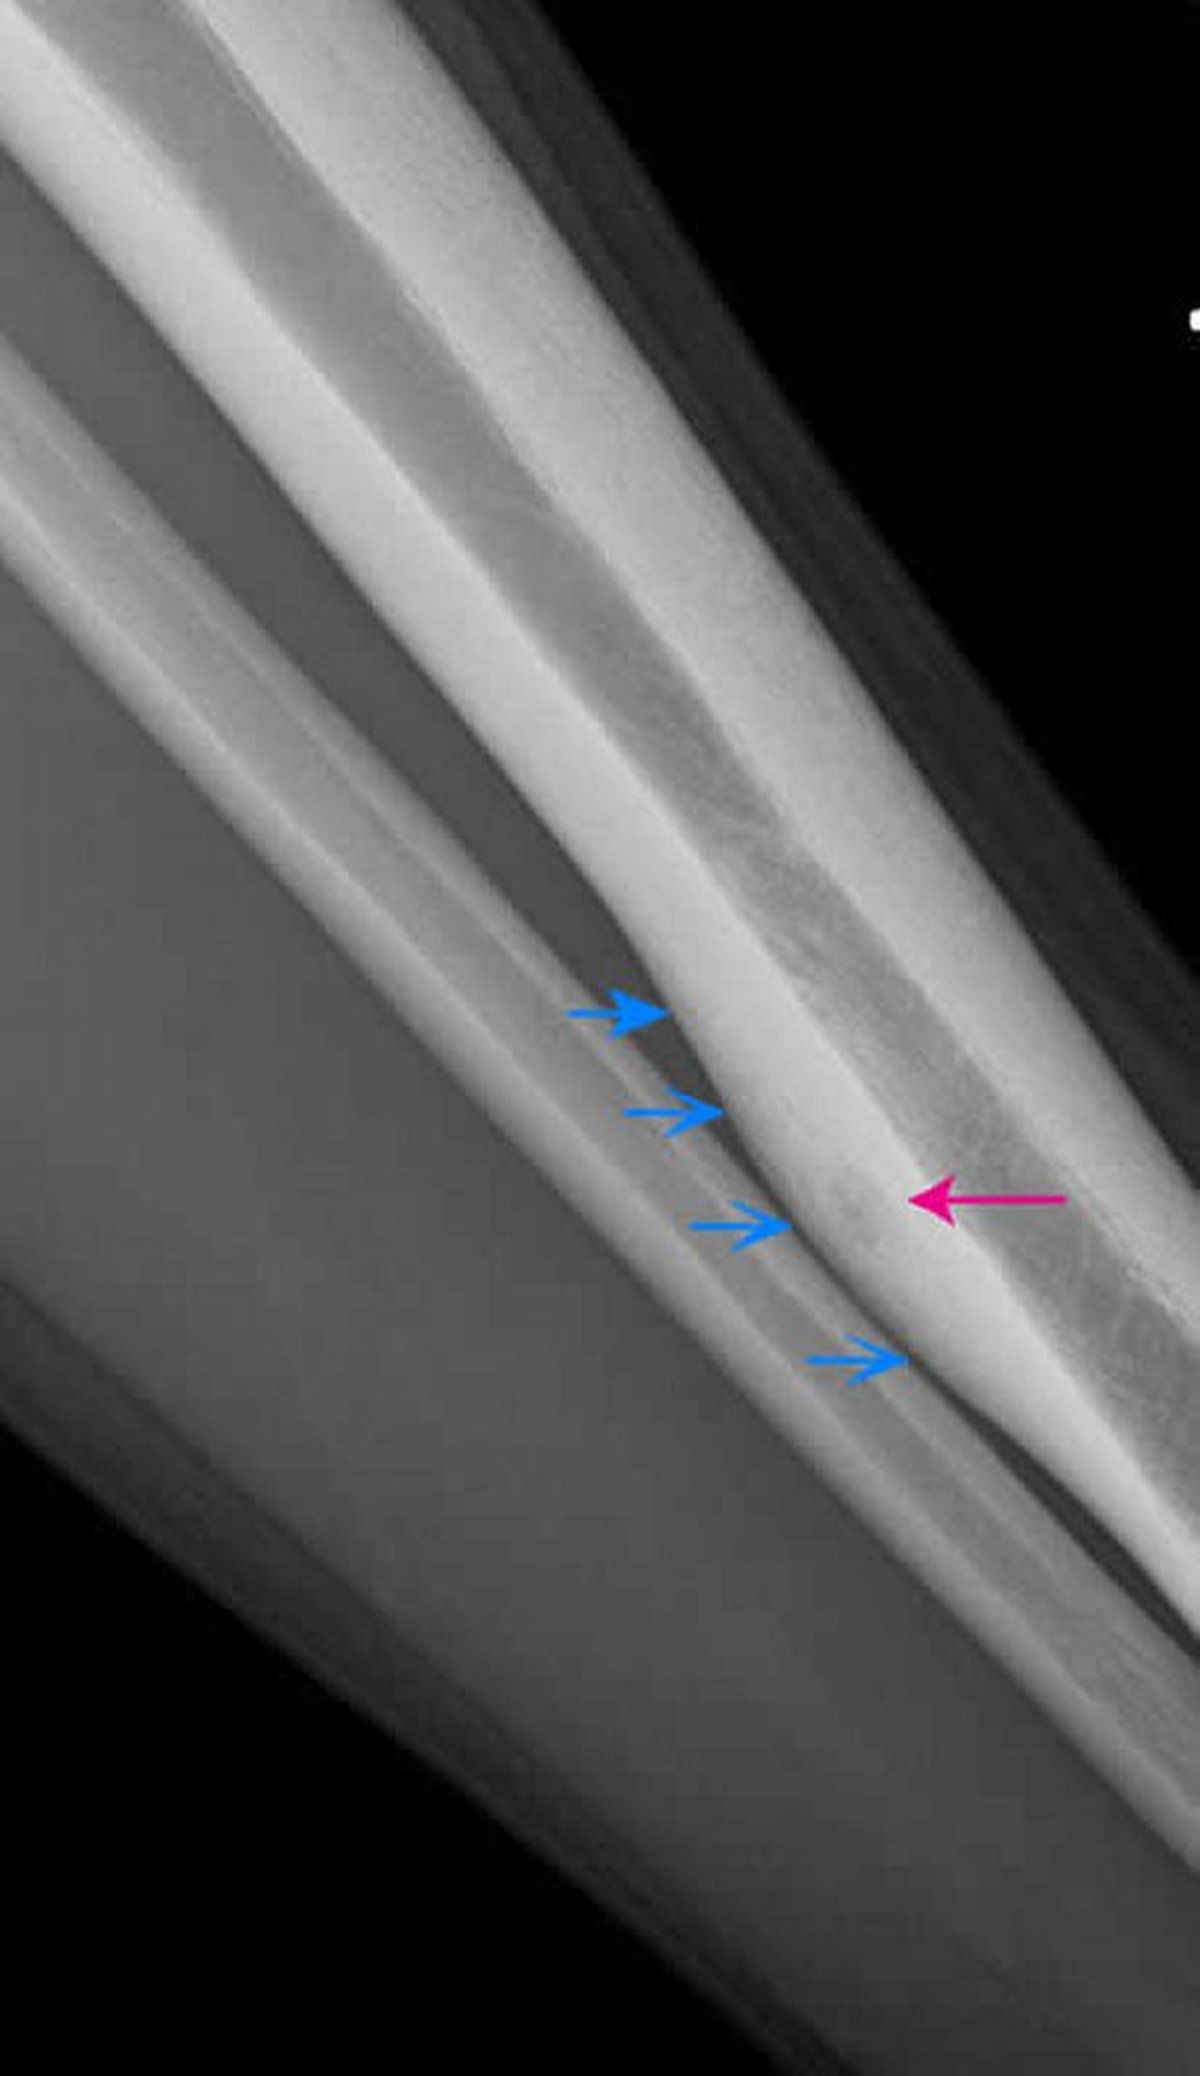

Остеоид-остеома большеберцовой кости (рентгенограмма)

На боковом рентгеновском снимке левой большеберцовой кости отмечается светлый участок в задней кортикальной зоне — остеоид-остеома (обозначена красной стрелкой). Обратите внимание на хронически возникающее, гладкое периостальное уплотнение вокруг опухоли (синие стрелки).

Image courtesy of Michael J. Joyce, MD, and Hakan Ilaslan, MD.